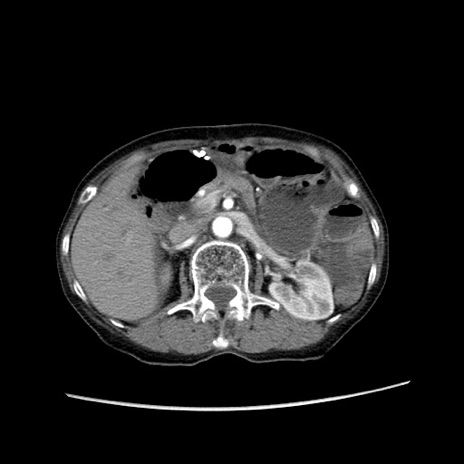

症例25(横断像)

【症例】80歳代女性

【主訴】胸のつかえ感

【現病歴】約9時間前に食後から胸のつかえた感じあり、嘔吐あり、来院。

【既往歴】胃癌(全摘)、胆摘、虫垂炎

【身体所見】心窩部に圧痛あり、反跳痛なし。

【データ】WBC 5700、CRP 0.05